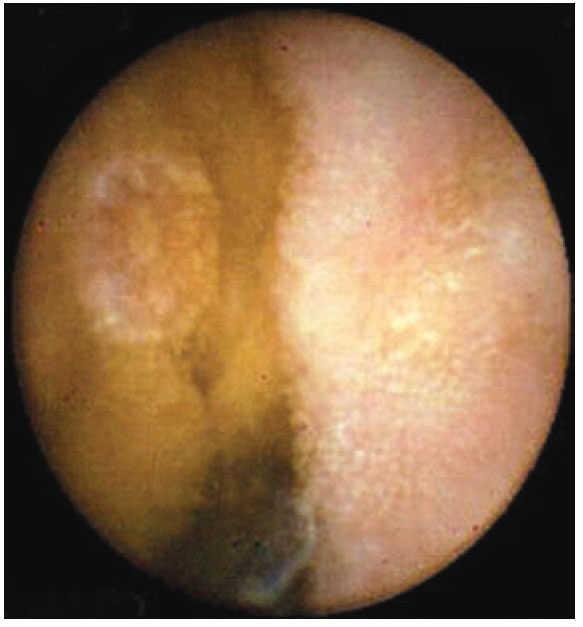

En todos los casos se administró la cápsula PillCam® de Given Imaging M2A. Se dio a deglutir con agua. Se utilizó un equipo de recuperación de imágenes que consta de nueve antenas receptoras, colocadas en todos los cuadrantes del abdomen, con un tiempo de grabación promedio de ocho horas. Al finalizar el estudio, se decodi- ficaron las imágenes en un programa diseñado para su lectura en computadora [Rapid Reader®] (figura 1). Los estudios fueron interpretados, cada uno en promedio de dos horas por los autores, que cuentan con experiencia en endoscopia, así como entrenamiento en la revisión de imágenes de cápsula endoscópica, apoyados por un atlas elaborado por expertos en estudios de cápsula endoscópica. Se registraron los hallazgos de todos y cada uno de los pacientes, emitiendo un reporte final por escrito, del cual se conservó una copia. Cabe mencionar que no hubo dificultades técnicas con el manejo de las imágenes. Para el estudio se realizó una hoja de captación de datos, donde quedaron registrados el número progresivo de estudio, iniciales del paciente, sexo, edad, motivo de envío y resultado del estudio de cápsula endoscópica. No se consignaron los recursos consumidos previamente por los pacientes (endoscopias, colonoscopias, internamientos, transfusiones, etc.), ya que en algunos casos acudían al estudio sin reportes previos.

Figura 1. Imagen normal. Vellosidades intestinales.